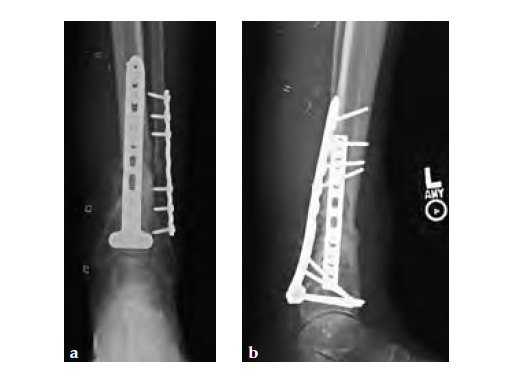

The posterior T-plates (pictured right) are available in 8-hole (132 mm), 12-hole (184 mm), and 16-hole (236 mm) lengths and should only be placed on the posterior aspect of the distal tibia. The plates are anatomically contoured to fit the posterior distal tibia. The plate edges have been rounded for a smoother insertion and provides less prominence. The plate has two locking strut screw holes to prevent collapse, four distal rafting locking screw holes and one proximal and one distal elongated hole to aid positioning. The design provides angular stability similar to a blade plate while maintaining ease of insertion.